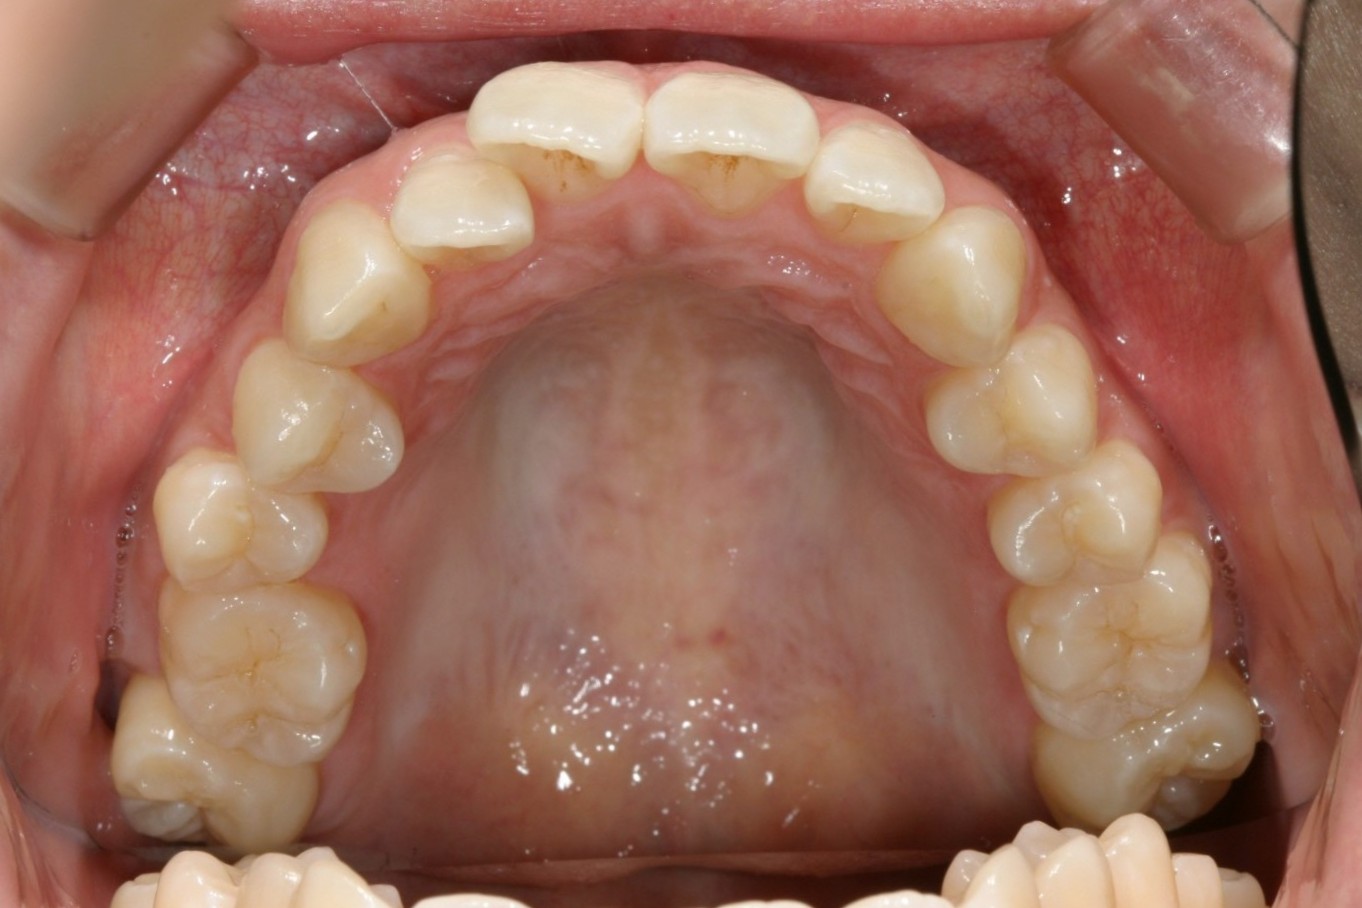

前歯が飛び出てねじれています。

少し出っ歯が目立ちます。